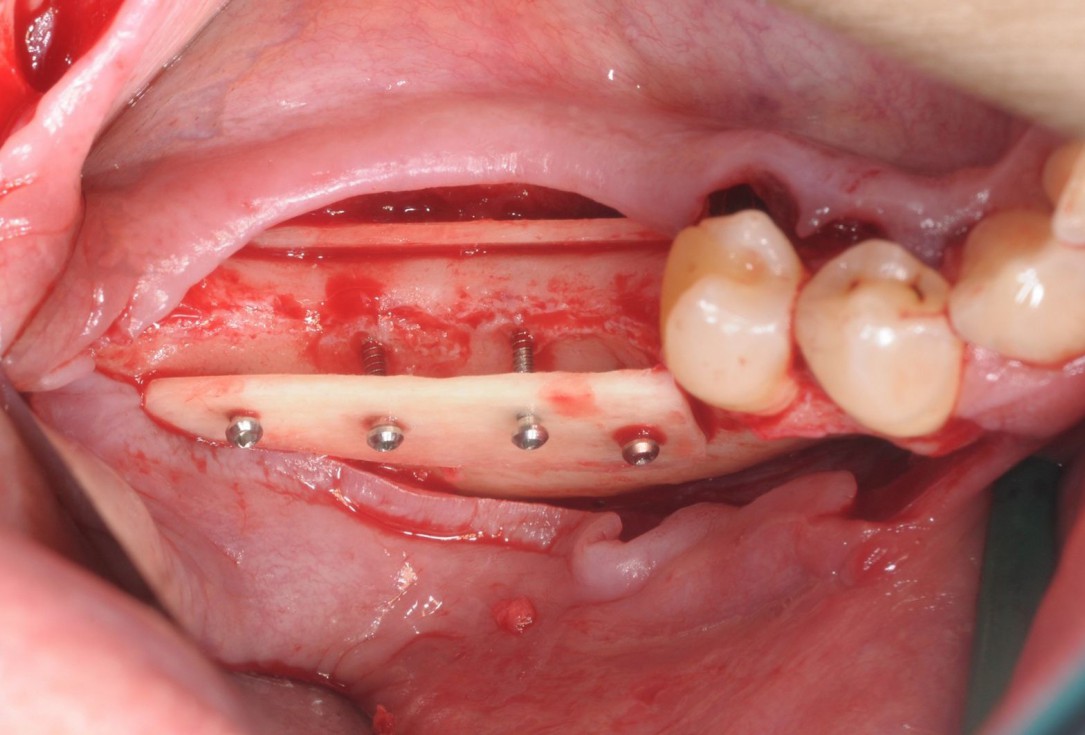

07/28 - Occlusal view on the immobile container created with the two cortical platesThree-dimensional augmentation with maxgraft® cortico - Dr. R. Würdinger